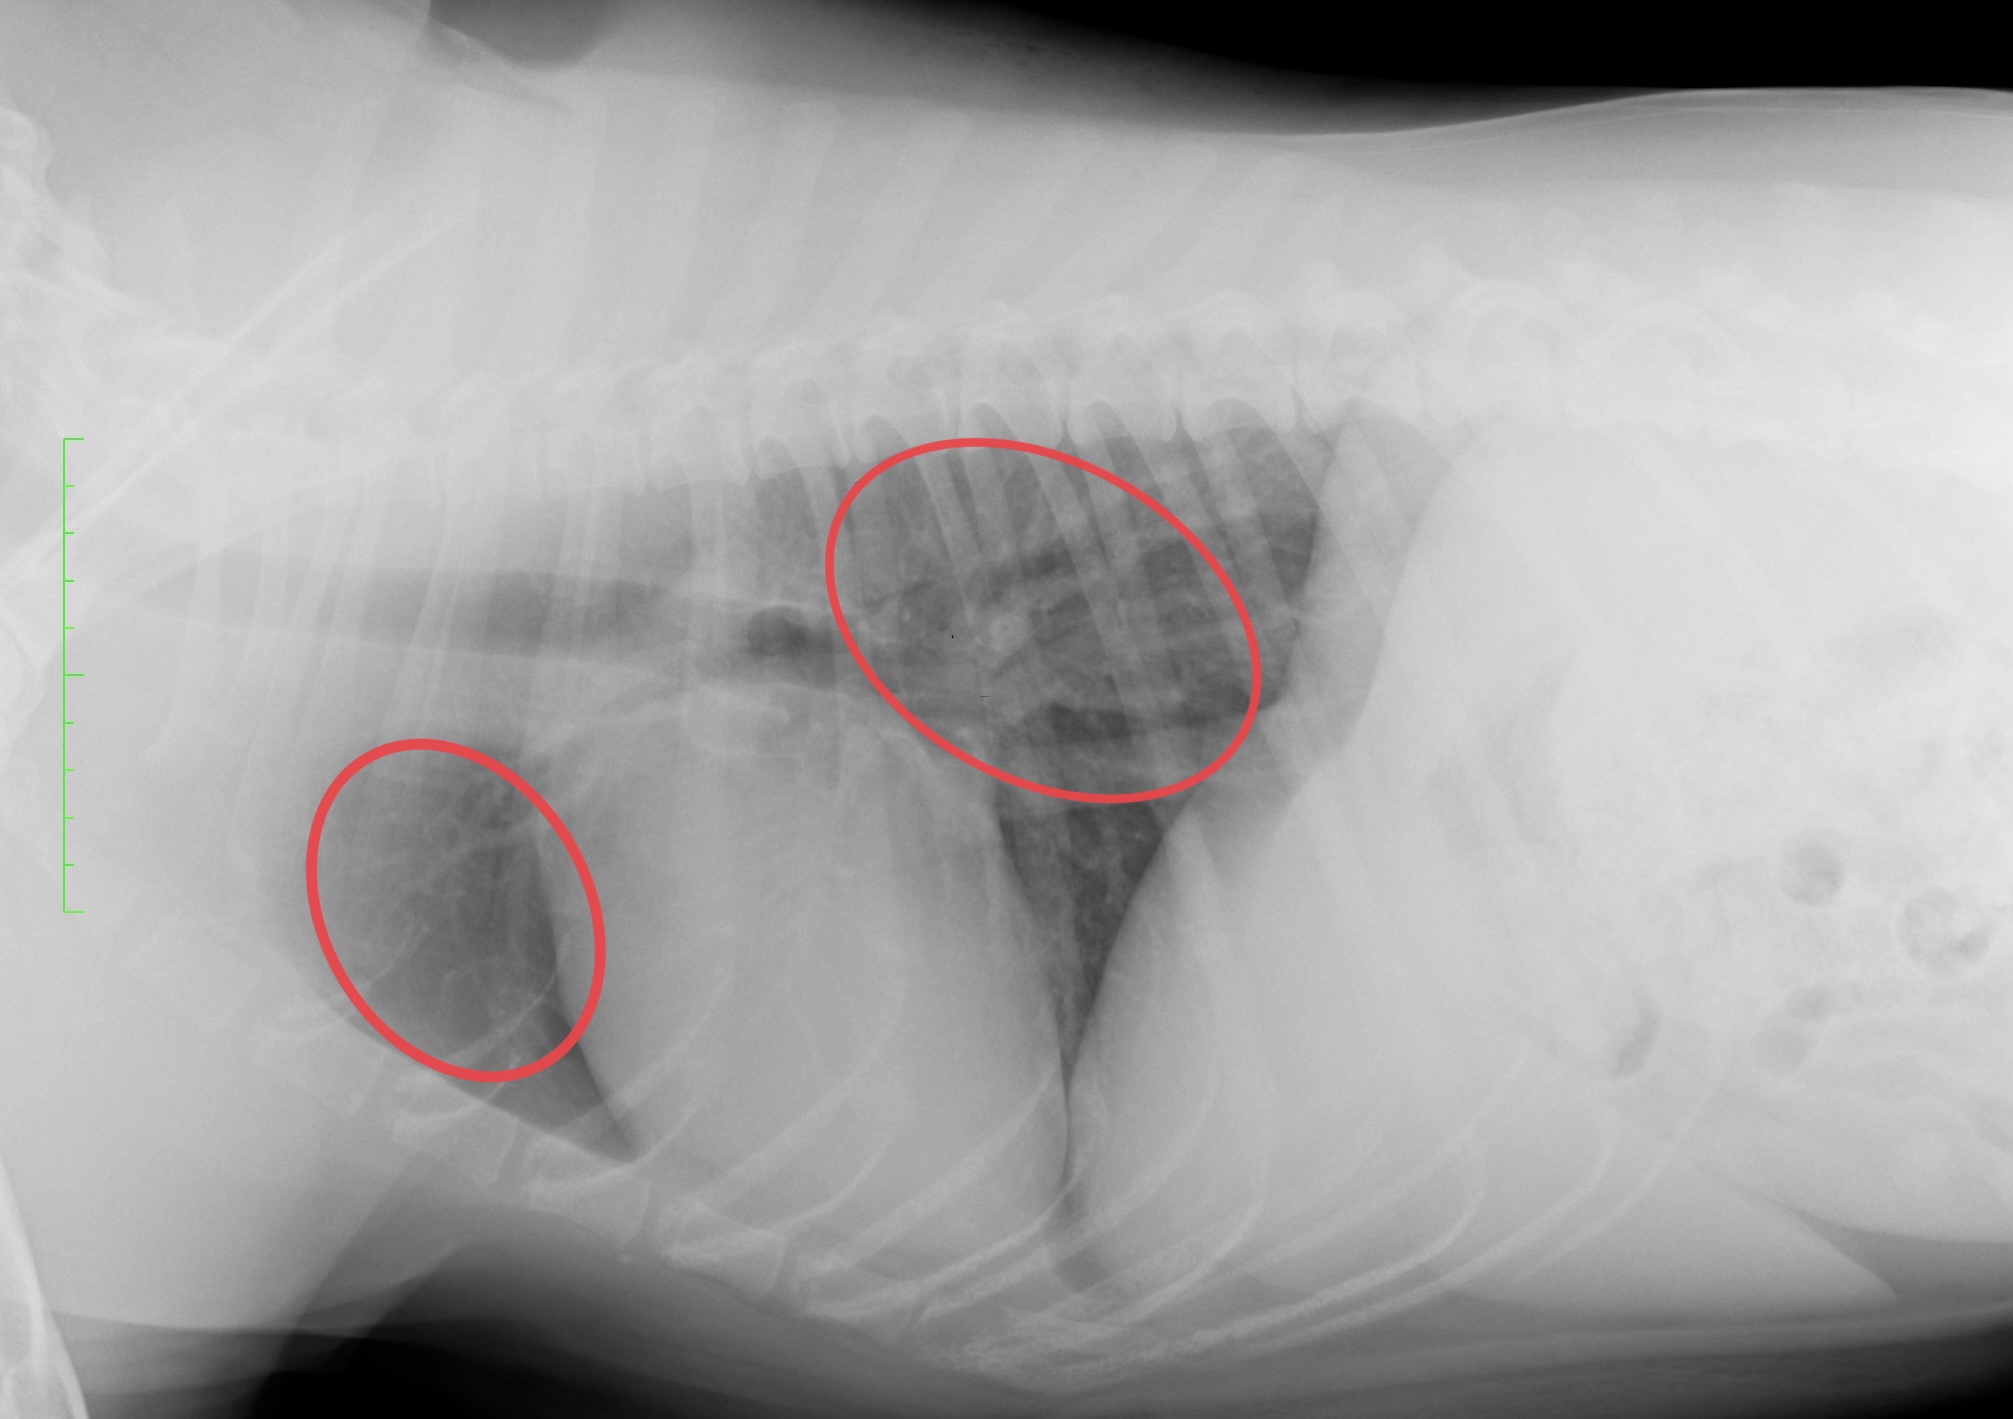

症状がひどくなり、肺炎へと進行してしまった場合、気管支の炎症像である気管支パターンというものがレントゲンで見えてきます。

肺炎へと進行してしまったレントゲン像